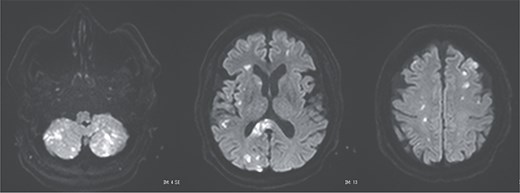

Postoperative magnetic resonance imaging showing diffuse cerebral infarctions.

A 70-year-old woman presented to the emergency department with sudden-onset chest and back pain. Contrast-enhanced CT revealed an ATAAD extending from the ascending aorta to the bilateral common iliac arteries. The primary entry tear extended from the ascending aorta into the aortic arch, and the false lumen remained patent throughout its entire peripheral extent (Fig. 1). Both renal arteries originated from the true lumen, and there was no malperfusion. Vital signs were stable, and the patient was not in shock. The patient underwent emergency total arch replacement with FET implantation using a 27 × 90 mm FROZENIX four-branched graft (Japan Lifeline Co., Ltd, Tokyo, Japan). The procedure was completed in 7 h and 6 min without intraoperative complications. Postoperatively, urine output declined markedly. Serum creatinine increased from a baseline of 0.81 to 2.61 mg/dl on postoperative Day 1. Diuretics failed to improve urine output, and renal replacement therapy was initiated. Contrast-enhanced CT on postoperative Day 2 showed no signs of renal malperfusion. Although the renal medulla exhibited normal enhancement, a diffuse non-enhancing area throughout the renal cortex—referred to as the “reverse rim sign”—was observed, consistent with RCN (Fig. 2). Thrombosis of the false lumen in the descending thoracic and thoracoabdominal aorta had progressed (Fig. 3). The patient developed persistent coagulopathy, with sustained hypofibrinogenemia and thrombocytopenia. On postoperative Day 2, the platelet count was 4.1 × 104/μl, D-dimer 13.5 μg/ml, and PT-INR 1.54, yielding an International Society on Thrombosis and Hemostasis DIC score of 6, consistent with overt DIC. Anticoagulation therapy with heparin and warfarin was administered. Ultimately, by postoperative Day 50, a total of 36 units of fresh frozen plasma and 100 units of platelets had been transfused; however, coagulation parameters gradually normalized thereafter, and no further transfusions were required (Fig. 4). A follow-up CT on postoperative Day 21 demonstrated further remodeling of the thrombosed false lumen. Brain magnetic resonance imaging performed on postoperative Day 9 to investigate delayed emergence revealed multiple scattered small acute ischemic infarctions involving the cerebellum, brainstem, and cerebral cortex (Fig. 5). These were not attributed to large-vessel occlusion but rather to systemic microthrombotic emboli. Despite supportive care, renal function did not recover, and maintenance dialysis was initiated. The patient was transferred to another hospital on postoperative Day 182.

DIC is frequently associated with acute kidney injury. Among them, RCN represents the most severe form, frequently resulting in irreversible renal failure. RCN is characterized by widespread coagulative necrosis due to decreased cortical perfusion. The renal cortex is more vulnerable to ischemia than the medulla because of its limited collateral circulation [4]. The “reverse rim sign,” defined by preserved medullary enhancement with cortical non-enhancement on contrast-enhanced CT, is a hallmark and highly specific imaging finding for RCN [5]. In DIC-associated RCN, systemic microthrombosis and regional hypoperfusion often cause irreversible cortical necrosis, leading to the need for long-term dialysis or kidney transplantation. In this case, RCN developed despite the absence of prolonged hypotension or renal artery malperfusion, suggesting a strong association with DIC. Diffuse RCN, as seen in the present case, is associated with worse renal outcomes than patchy RCN [6]. The advantage of diagnosing RCN, as opposed to typical acute kidney injury, is the ability to predict poor renal prognosis early on, allowing for earlier preparation for maintenance dialysis.

Postoperative DIC following ATAAD repair can compromise major organ function, including the kidneys and brain. Prompt diagnosis and appropriate anticoagulation may be essential to improve patient outcomes. Although recombinant thrombomodulin has been reported to be effective in DIC, its use may be contraindicated in cases with high bleeding risk [7]. In our case, the presence of widespread cerebral infarctions raised concern for hemorrhagic transformation; thus, thrombomodulin was not administered.